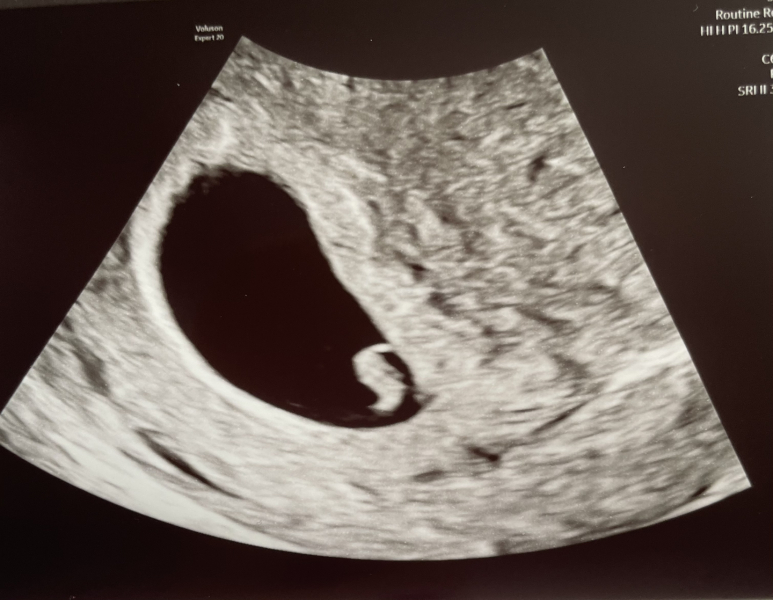

Hello lovelies, just a little happy update from me (finally). I had my scan at EPU today and for the first time ever we've come out of there with hopeful news.

One little 'seahorse' as the sonographer put it, with a lovely heartbeat and measuring 6+2, which is great as I'm 6+2 today. We've never had even remotely this much hope before, so we're fingers crossed and onwards how šŸ¤ž

@KittyFantastica what a great news to have this morning! The scan is so clear as well, did you see the yolk sac as well? I remember my son's scan at 7+2, it had this little bubble, and yes he did look like a little seahorse with a balloon. Congratulations and I really have everything crossed for you!

@KittyFantastica so happy for you! It is such a wonderful clear picture and really does look like a seahorse! Its so reassuring to have seen the heartbeat already. Lovely to have some positive news and make us all feel more hopeful šŸ„°ā¤ļø xx

@KittyFantastica - such wonderful news and a lovely scan photo too. I’m so happy for you!

Thank you @Lemonbalm8

yes we could see the yolk sac, she moved the probe so that the embryo was in front of it for the photo. It was the clearest way to see the heartbeat too. Blew our minds! I think at this stage I’m grateful not to be feeling sick all the time, but we never know what will be around the corner šŸ˜…

Oh @KittyFantastica this is brilliant news on a gloomy Tuesday!! So so happy to hear that and see your lil seahorse šŸ’œšŸ’œšŸ’œ